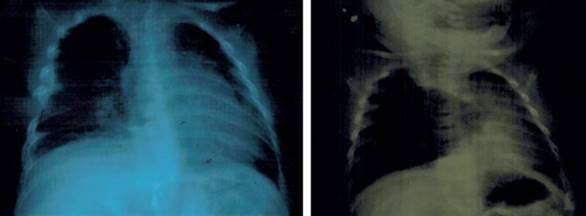

Se solicitó una radiografía de tórax que se repitió a las 24 horas. Ambas evidenciaron una imagen radiolúcida, a nivel de lóbulo medio derecho, redondeada, con bordes bien limitados, con contenido aéreo (Figura 1). Por sus características imagenológicas y por el estado clínico de la niña no se planteó que se tratara de un neumotórax. Teniendo en cuenta la edad se sospechó una malformación pulmonar, aunque llamaba la atención que no hubiera tenido síntomas sugestivos antes.

Figura 1: Radiografías realizadas el día del ingreso y a las 24 horas posteriores